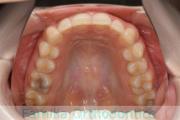

- ≫治療前

上顎

下顎

前歯の関係など

- ≫治療後